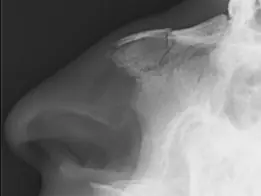

Epaule Humerus Coude/Avant-bras Bassin Fémur Genou Cheville Pied Main Maxillo-facial Rachis Anticoagulation préventive TC léger